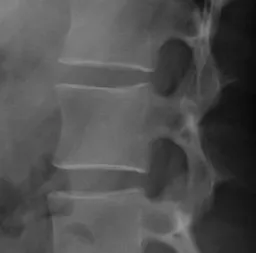

A normal hip joint (Wikipedia)

On the upper left is the pelvic bone with its socket-style hip joint. Rising from the lower right is the top of the femur with its ball fitting into the socket.